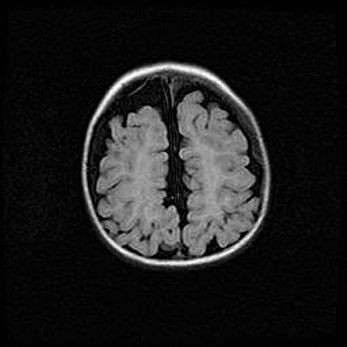

Наружная гидроцефалия с возможной атрофией височных областей.

Возраст: 28 дней

Вес: 3670 г

Пол: мужской

Окружность головы: 38 см

Срок гестации: 40 недель

Гидроцефалия головного мозга у новорожденных – это заболевание, которое характеризуется скоплением избыточного количества спинномозговой жидкости в желудочковой системе головного мозга в результате затруднения её перемещения от места выработки к месту поглощения в кровеносную систему или вследствие нарушения абсорбции. При открытой наружной форме гидроцефалии у новорожденных расширяются и переполняются субарахноидные пространства.

При нормотензивных  формах,  которые,  как  правило,  являются  следствием  перенесенных ишемических  повреждений  паренхимы  мозга,  возможно  сочетание микроцефалии  с нормотензивной гидроцефалией. В основе данных изменений лежит атрофия больших полушарий с преимущественной  локализацией  в  лобно-височных  областях.